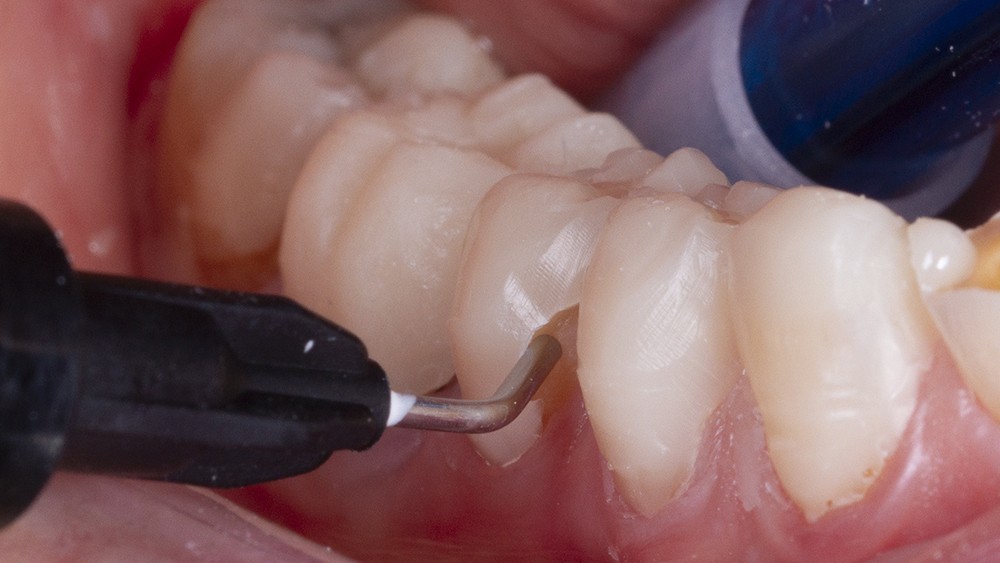

Un sablage à l’oxyde d’alumine est recommandé lorsque les usures sont marquées afin de préparer la surface de collage. Après rinçage, un mordançage à l’acide orthophosphorique est réalisé pendant 30 secondes sur l’émail et 15 secondes sur la dentine. Après un rinçage scrupuleux, un adhésif est étalé sur l’ensemble des surfaces mordancées, soufflé puis photopolymérisé (fig. 5).

L’option utilisant des composites nano-hybrides nécessite, au préalable, de les déposer en quantité suffisante dans la clé transparente (fig. 6). Celle-ci est ensuite repositionnée sur les dents et les composites sont photopolymérisés à travers la clé.

Le remplissage du moule au composite doit se faire a minima ; il est en effet plus simple de compléter les quelques manques de matériaux en bénéficiant de la pellicule d’inhibition à l’oxygène que de retirer des excès conséquents. Il est aussi recommandé de procéder à une double enduction en injectant directement le composite flow dans les cavités érosives en parallèle du remplissage de la clé. Les excès relatifs de composites seront éliminés après polymérisation complète à l’aide d’une lame froide de bistouri ou d’une fraise adaptée de faible granulométrie.

Un polissage des surfaces résineuses est nécessaire pour finaliser la temporisation (fig. 7).